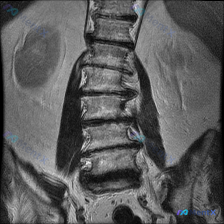

腰椎MRI示右侧弯+多节段退变,这个病例真的只是退变性侧弯吗?

整理到一份腰椎冠状位MRI影像资料,先给大家看客观表现:

- 脊柱力线:腰椎向右侧侧弯

- 椎体:高度、排列大致连续,无明显滑脱,骨质信号未见明确局灶异常

- 椎间盘:普遍T2低信号(脱水退变),下腰椎(L3/4-L5/S1)椎间隙变窄,冠状面见轻度周边膨隆

- 小关节:多节段骨质增生、间隙窄,呈退行性改变

- 骶髂关节:间隙尚清晰,未见明显骨质破坏/侵蚀

- 软组织:旁椎肌肉未见明确异常信号或肿块

影像小结首先报了「腰椎侧弯畸形、多节段椎间盘/小关节退变」。